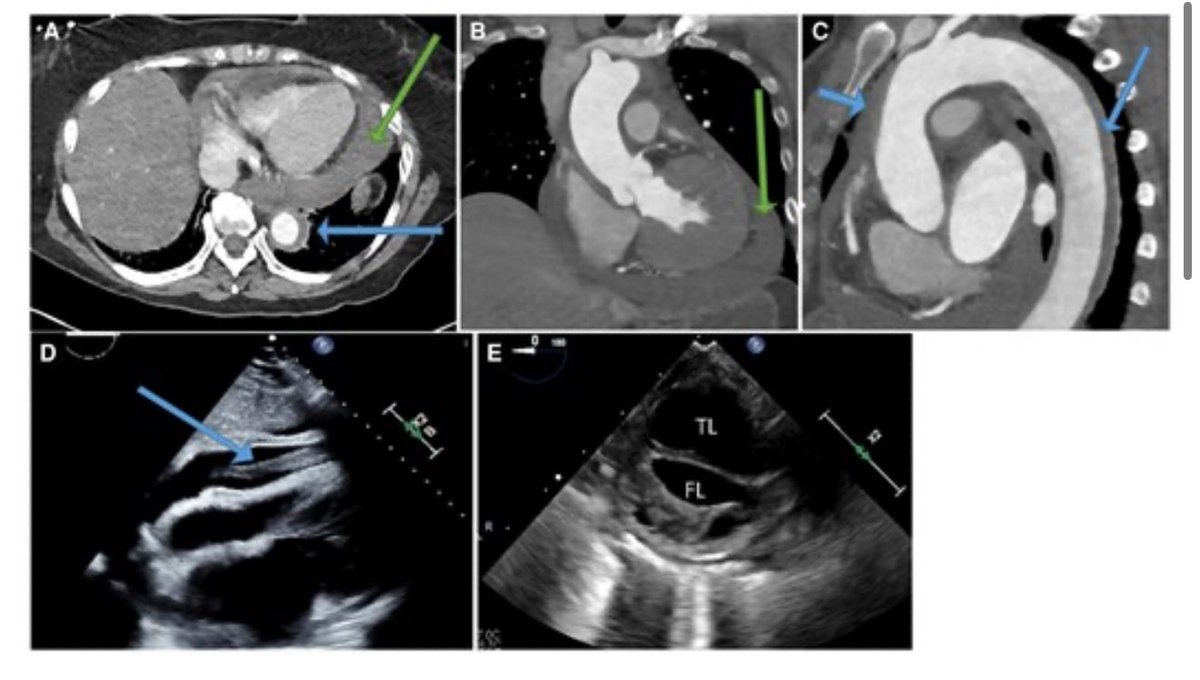

#EHJIMP Abscence of a #dissection flap on CT cannot fully exclude an acute aortic syndrome and that the appearance of aortic mural thickening should raise suspicion for intramural haematoma ➡️ https://t.co/i3rKHl7Z6y